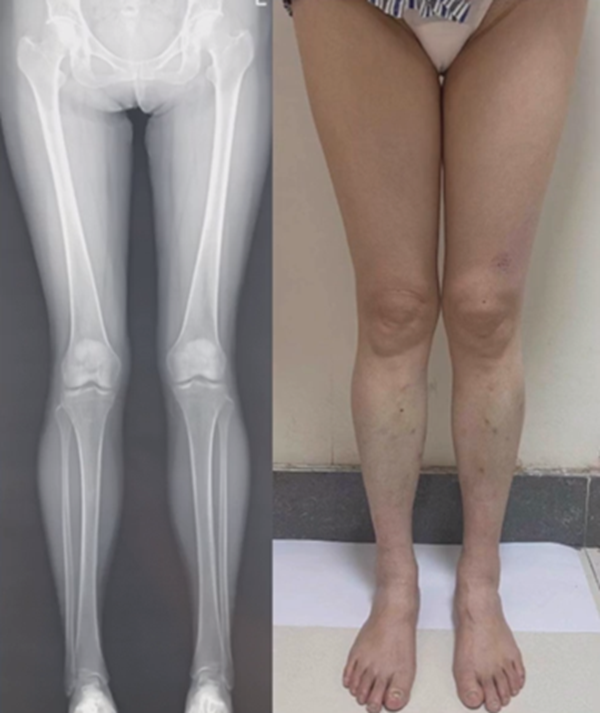

病例,X患者,女,双侧外翻膝,行双侧DFO。

术后6周摔伤,一侧出现膝内翻。

影像学检查显示左侧出现合页断裂。

进行翻修,术前力线显示内翻。